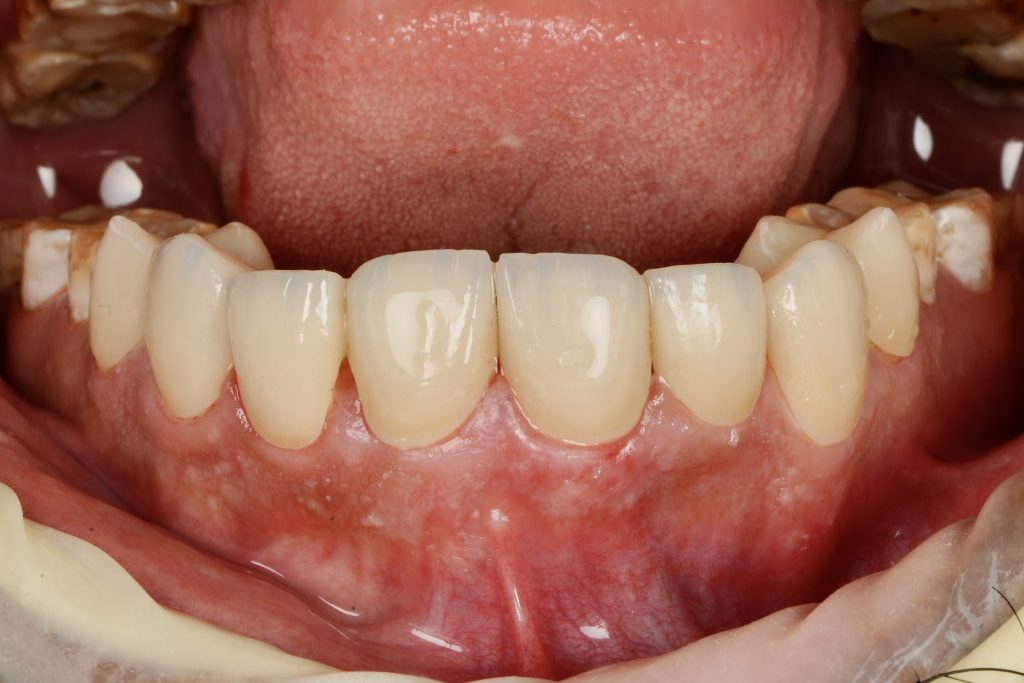

Each veneer was etched with 9 % HF acid for 20 seconds, silanated, and dried. Teeth were treated with 37 % phosphoric acid and universal adhesive (Clearfil Universal Bond Quick). Light-cure resin cement (Variolink Esthetic LC) was applied under full-arch rubber-dam isolation. Excess cement was removed and polymerization performed for 40 s per surface (Fig 4).

Margins were refined using fine diamond strips, and surface gloss was enhanced with a multi-step polishing system (Shofu OneGloss + OptraPol Next Gen). Post-operative evaluation showed ideal incisal translucency, line-angle symmetry, and gingival health (Fig 5 & 6).